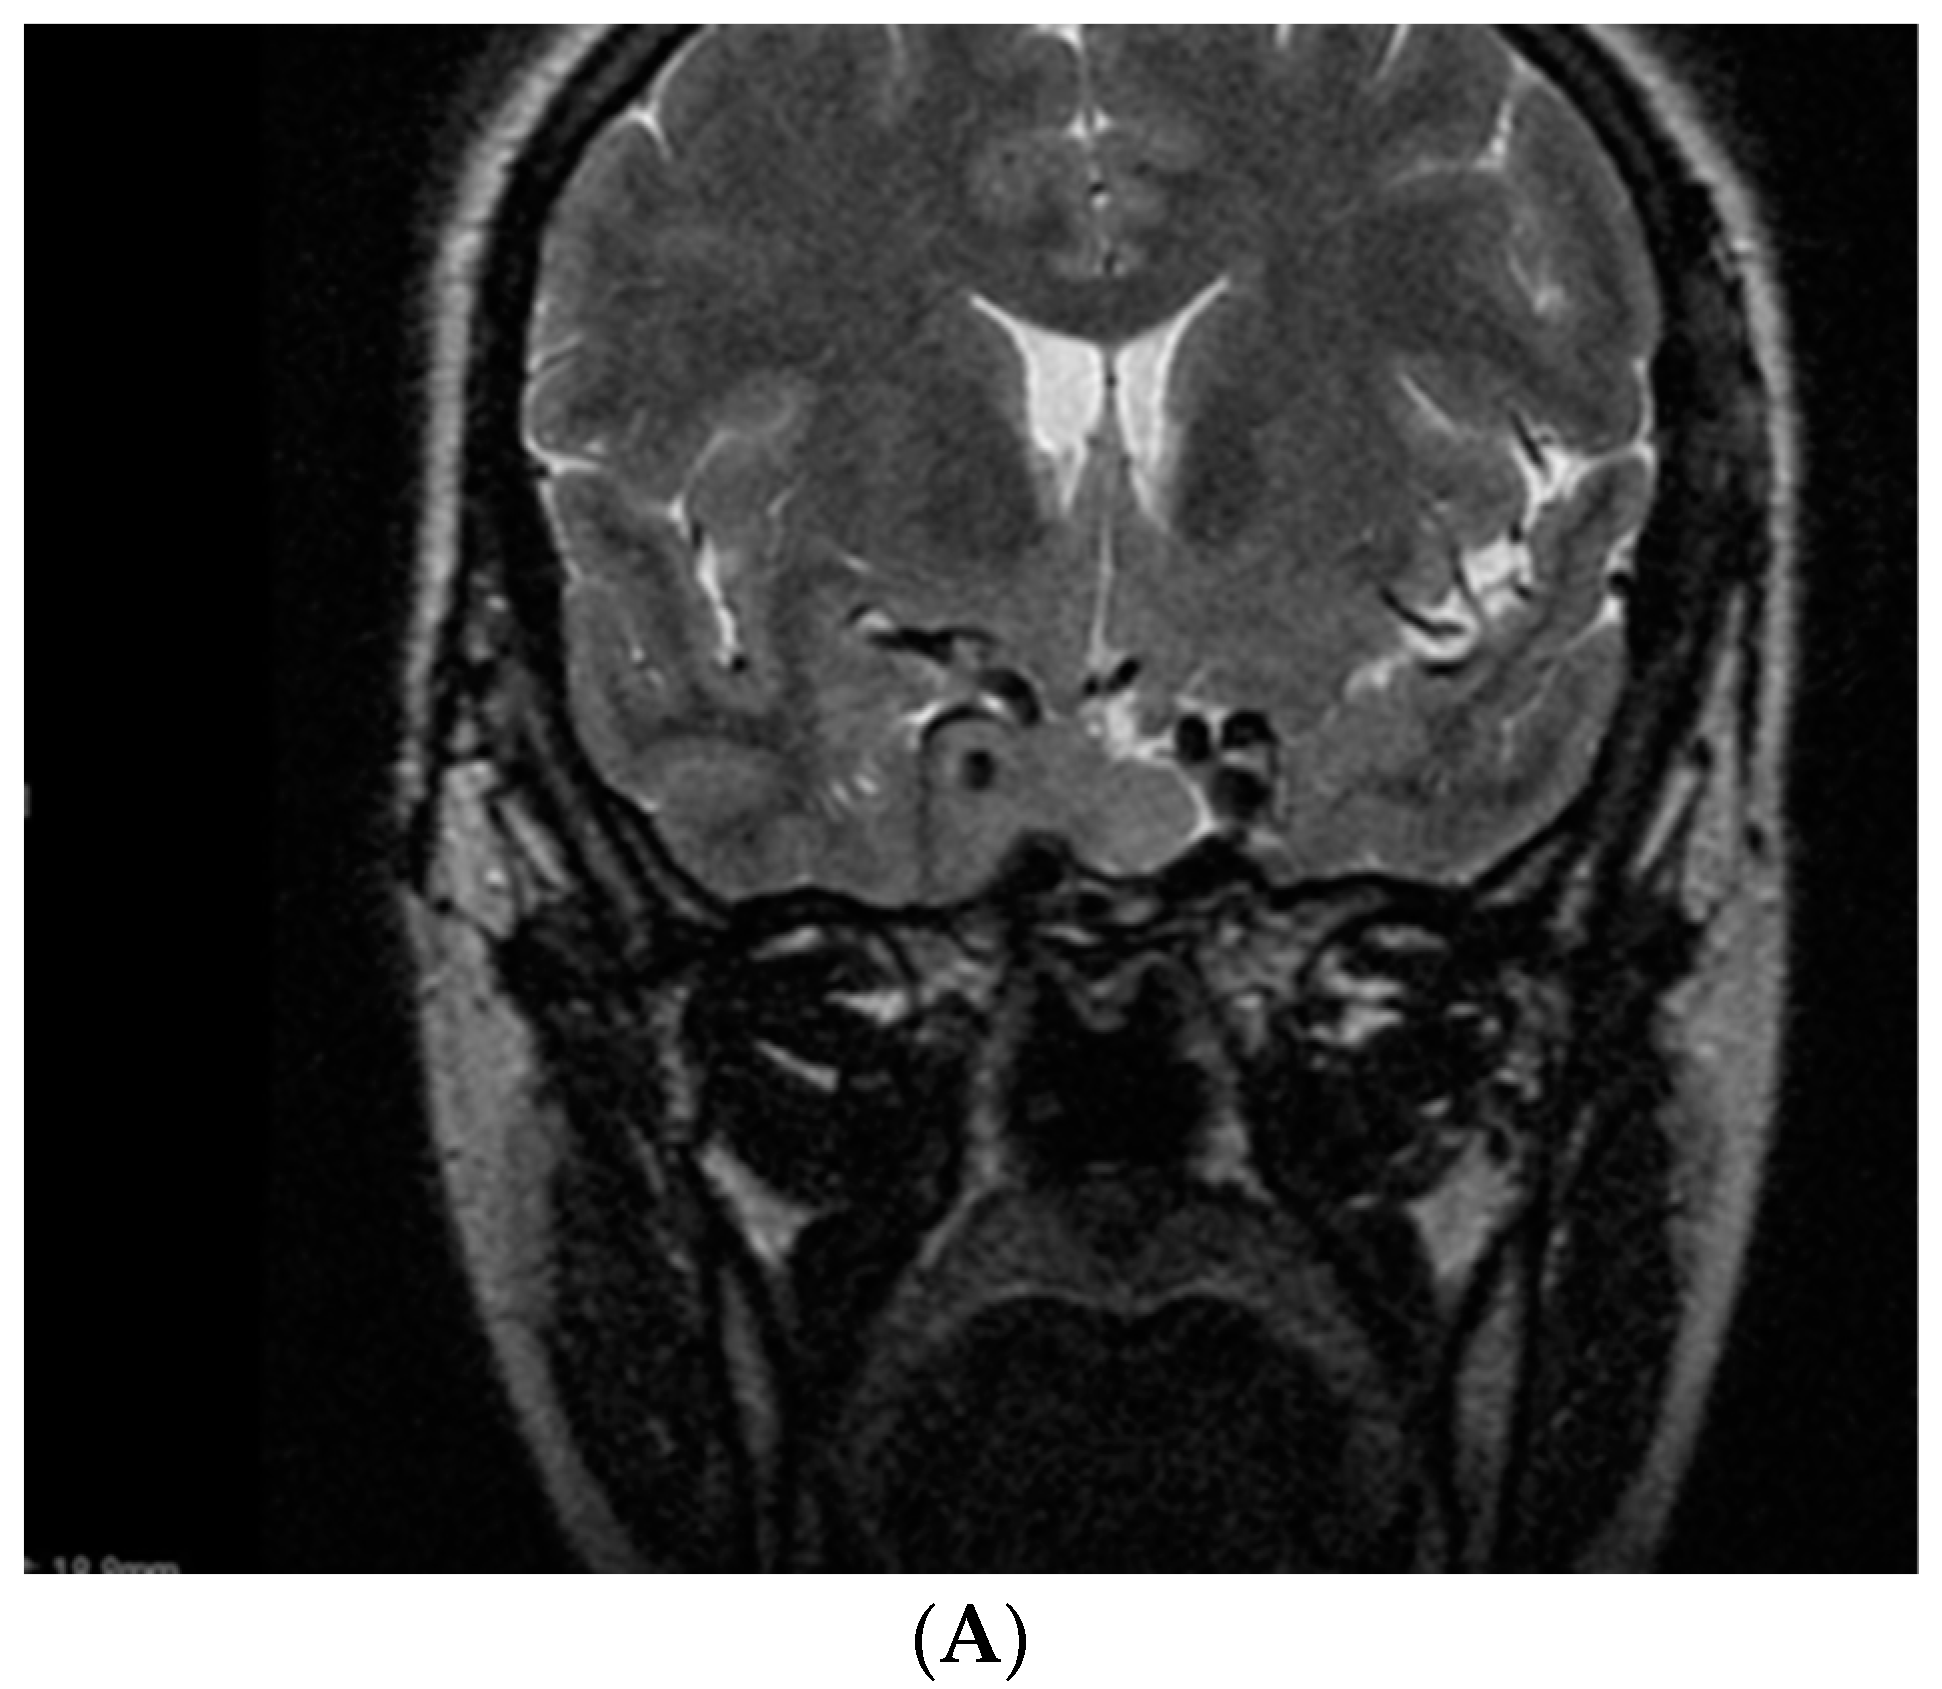

- Dicuonzo, F.; Purciariello, S.; De Marco, A.; Guastamacchia, E.; Triggiani, V. Inoperable Giant Growth Hormone-secreting Pituitary Adenoma: Radiological Aspects, Clinical Management and Pregnancy Outcome. Endocr. Metab. Immune Disord. Drug Targets 2019, 19, 214–220. [Google Scholar] [CrossRef]